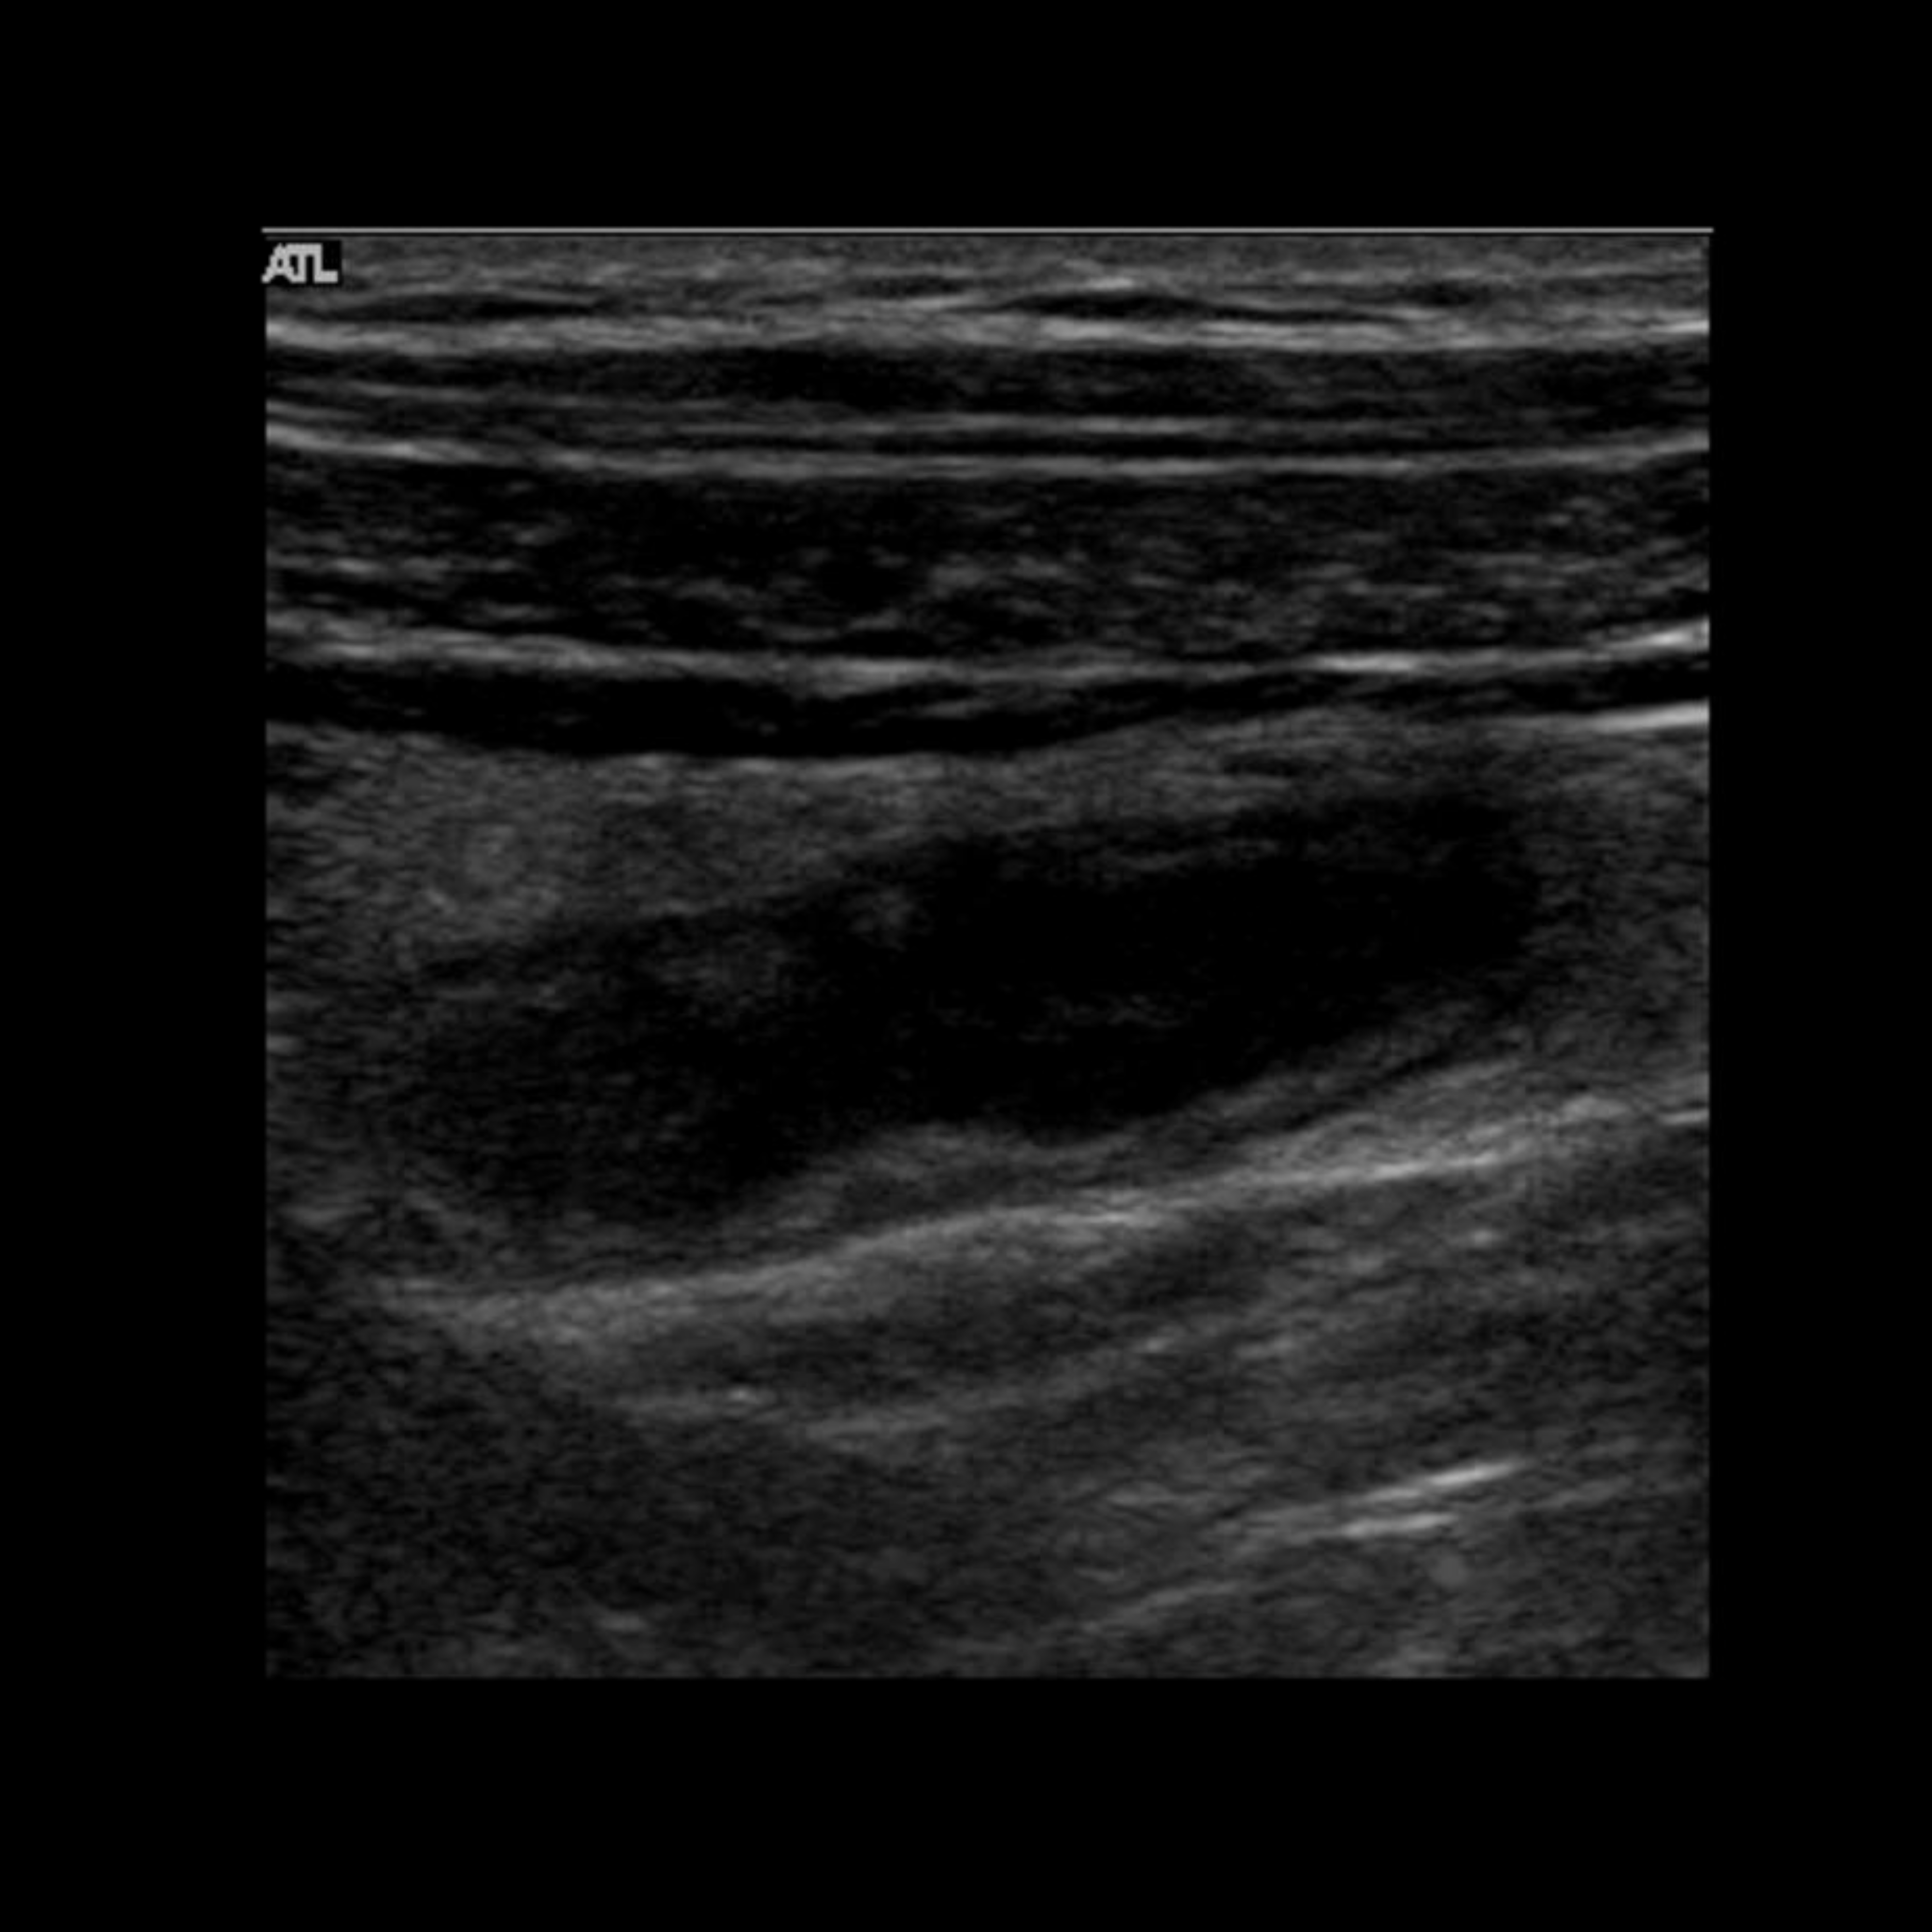

Appendicitis 5

1.5 cm appendicitis with hyperemia.